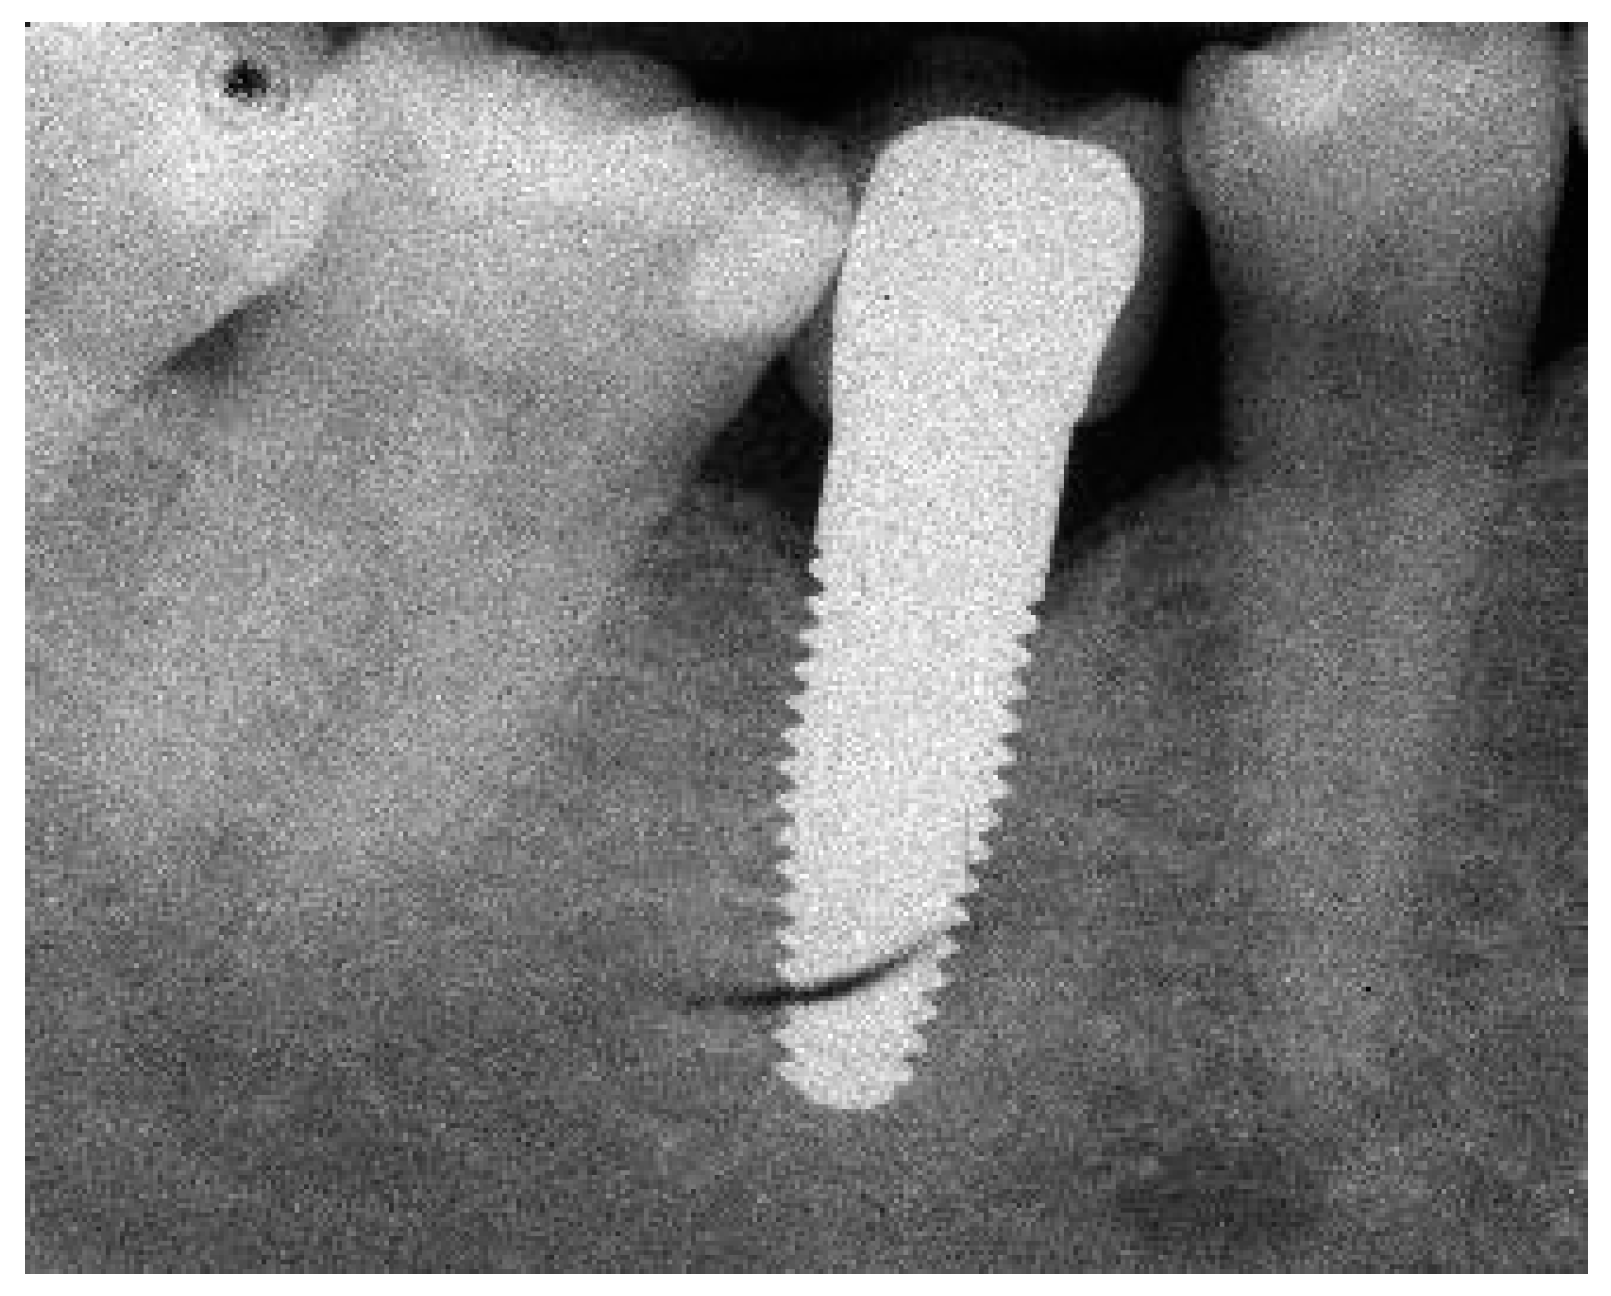

Figure 1.

(a) Exemplary radiograph at the 5-year follow-up depicting a single-tooth implant with a distinct vertical defect at the mesial and distal aspect of the implant. The lower corner of the straight cylindrical implant part was used as reference point for bone level calculations. (b) Clinical situation of the same implant prior to removal.

3.3. Marginal Bone Remodelling

From implant insertion (II) to PI, the mean marginal bone loss was 1.13 mm and from II to the 1-year follow-up it was 1.31 mm. A bone loss of 1.45 mm between II and the 3-year follow-up and of 1.12 mm between II and the 5-year follow-up was found. The results indicate that there was a slight further increase in bone loss from the 1-year to the 3-year follow-up but a decrease in bone loss from the 3-year to the 5-year follow-up (Table 7). At the 5-year follow-up, at 11 of 41 eligible implants (27%), a marginal bone loss of more than 2 mm was detected. Of these 11 implants, 5 demonstrated more than 3 mm of bone loss. This resulted in a 73% success grade I and to 88% success grade II after 5 years [26]. An exemplary radiograph and clinical picture show the typical bone loss pattern (Figure 1). Regarding any influence or correlation of baseline parameters, the performed univariate analysis did not disclose any effect or correlation of these parameters onto the bone remodelling/loss from implant insertion to the 5-year follow-up (Table 8).